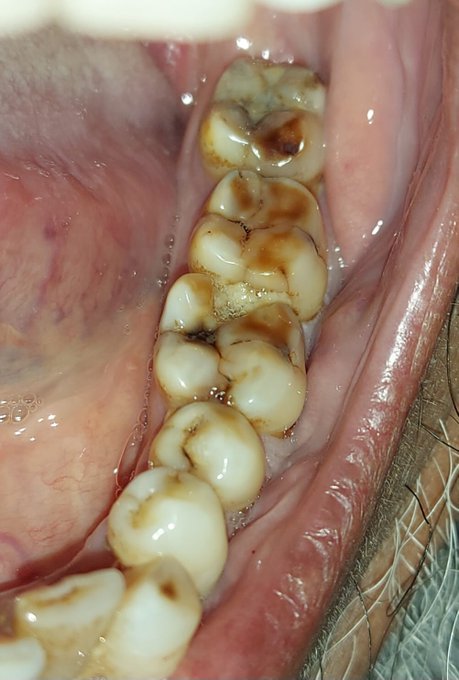

Clinical examination showed caries involving distal surface of tooth no.36 along with food impaction. Diagnosis irreversible pulpitis in tooth no.36